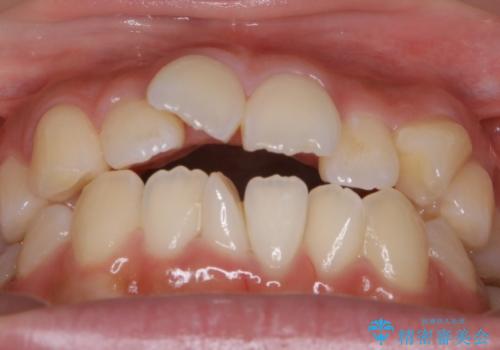

- 上下の歯のガタつきを主訴にご来院されました。

前歯部に特にガタつきが見られ、正中もズレている状態でした。

矯正装置の希望がインビザラインだったため、マイクロインプラントを併用し、奥歯から順に遠心移動をかけていくことにより非抜歯でも主訴のガタつきを治すことができました。

術前・術後の笑った時の歯の見え方の変化にも注目してみてください!